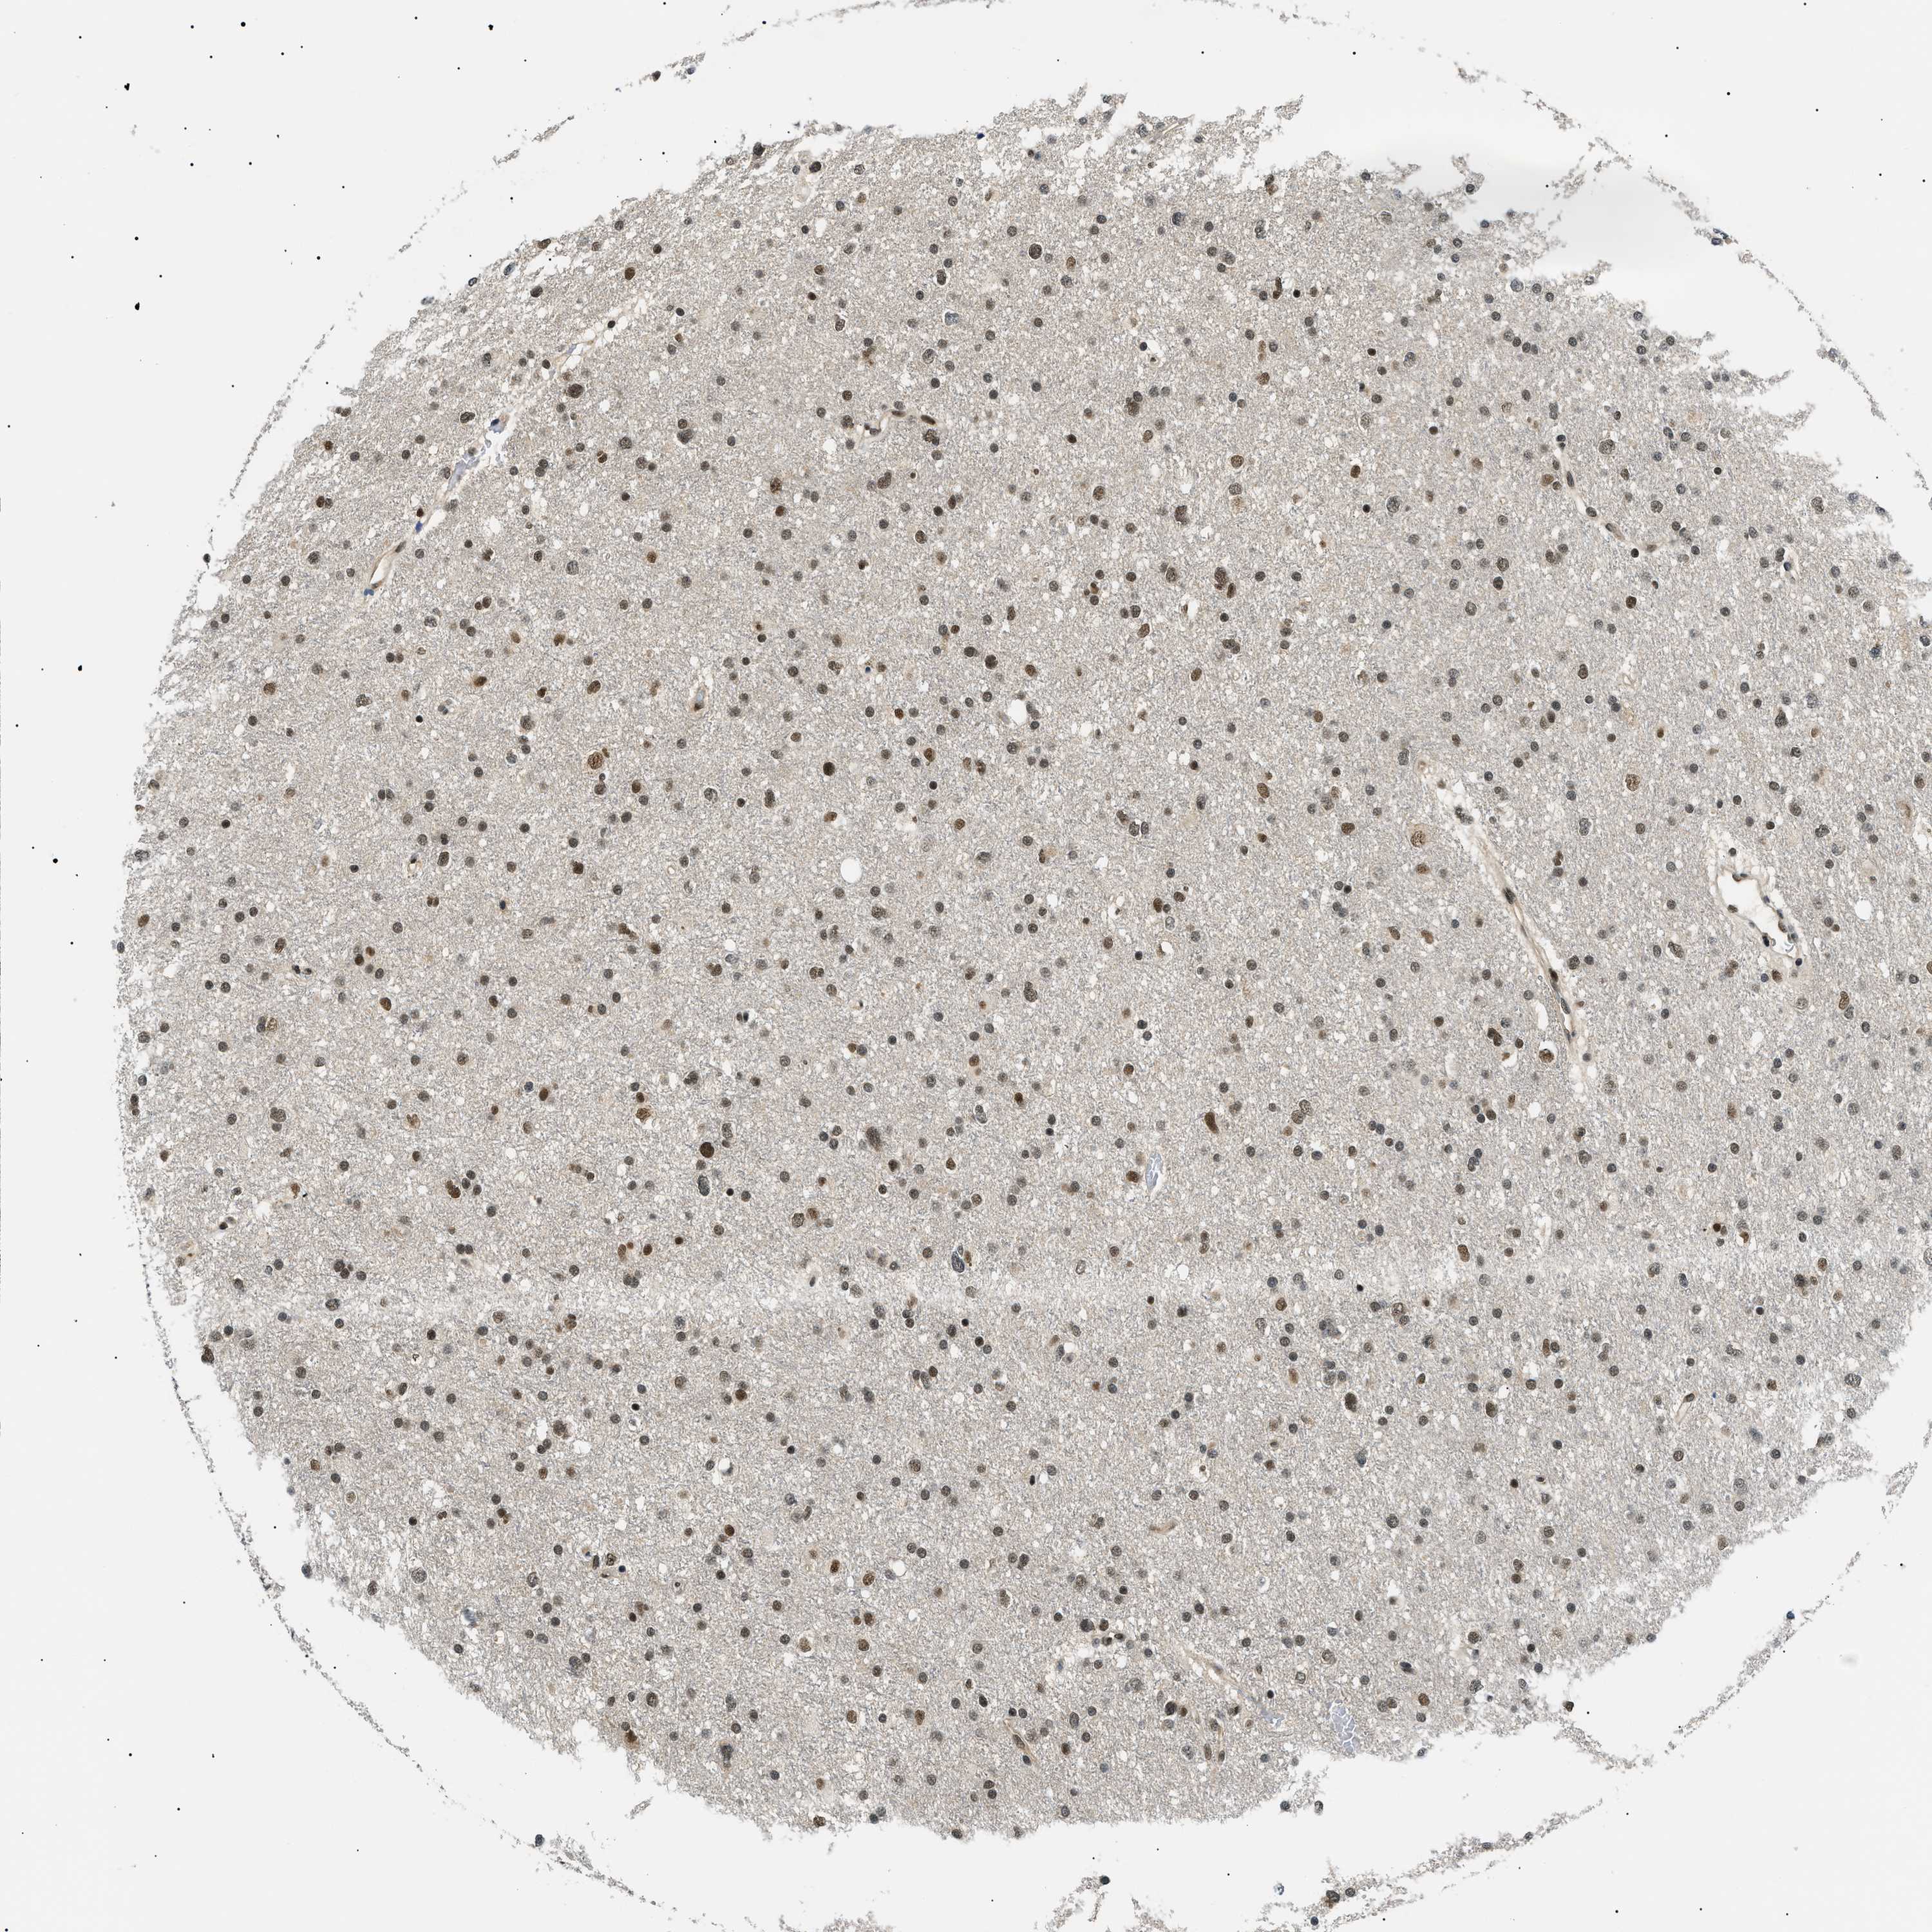

GLIOMA - Protein expressioni

A mouse-over function shows sample information and annotation data. Click on an image to view it in a full screen mode. Samples can be filtered based on level of antibody staining by selecting one or several of the following categories: high, medium, low and not detected. The assay and annotation is described here.

Note that samples used for immunohistochemistry by the Human Protein Atlas do not correspond to samples in the TCGA dataset.

Antibody stainingi

Antibody staining in the annotated cell types in the current human tissue is reported as not detected, low, medium, or high, based on conventional immunohistochemistry profiling in selected tissues. This score is based on the combination of the staining intensity and fraction of stained cells.

Each image is clickable and will lead to virtual microscopy that enables deeper exploration of all samples and also displays staining intensity scores, fraction scores and subcellular localization as well as patient and tissue information for each sample.

Antibody HPA019824

Antibody CAB015201

Staining

High

Medium

Low

Not detected

Intensity

Strong

Moderate

Weak

Negative

Quantity

>75%

75%-25%

<25%

None

Location

Nuclear

Cytoplasmic/membranous

Cytoplasmic/membranous,nuclear

Glioma, malignant, High grade

Glioma, malignant, Low grade